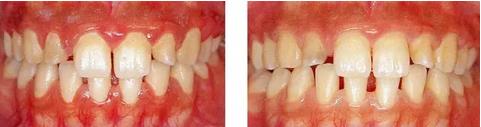

圖16-1(左) 主訴為前牙處的美學問題的55歲男性患者的初診時的口腔正面照。上頜前牙處的修復體有大小不合適、形態(tài)等為題,處于不容易被清潔的狀態(tài)。另外,上頜前牙處的牙齦非常薄,露出修復體邊緣的狀態(tài)。這種狀態(tài)很有可能會讓牙齦附著進一步喪失。

圖16-2(右) 戴上最終修復體8年后的狀態(tài)。進行了去除牙周袋以及獲得附著牙齦為目的的牙周外科,制作了便于清潔的修復體,這樣一來就可以維持安定的口腔內狀態(tài)。